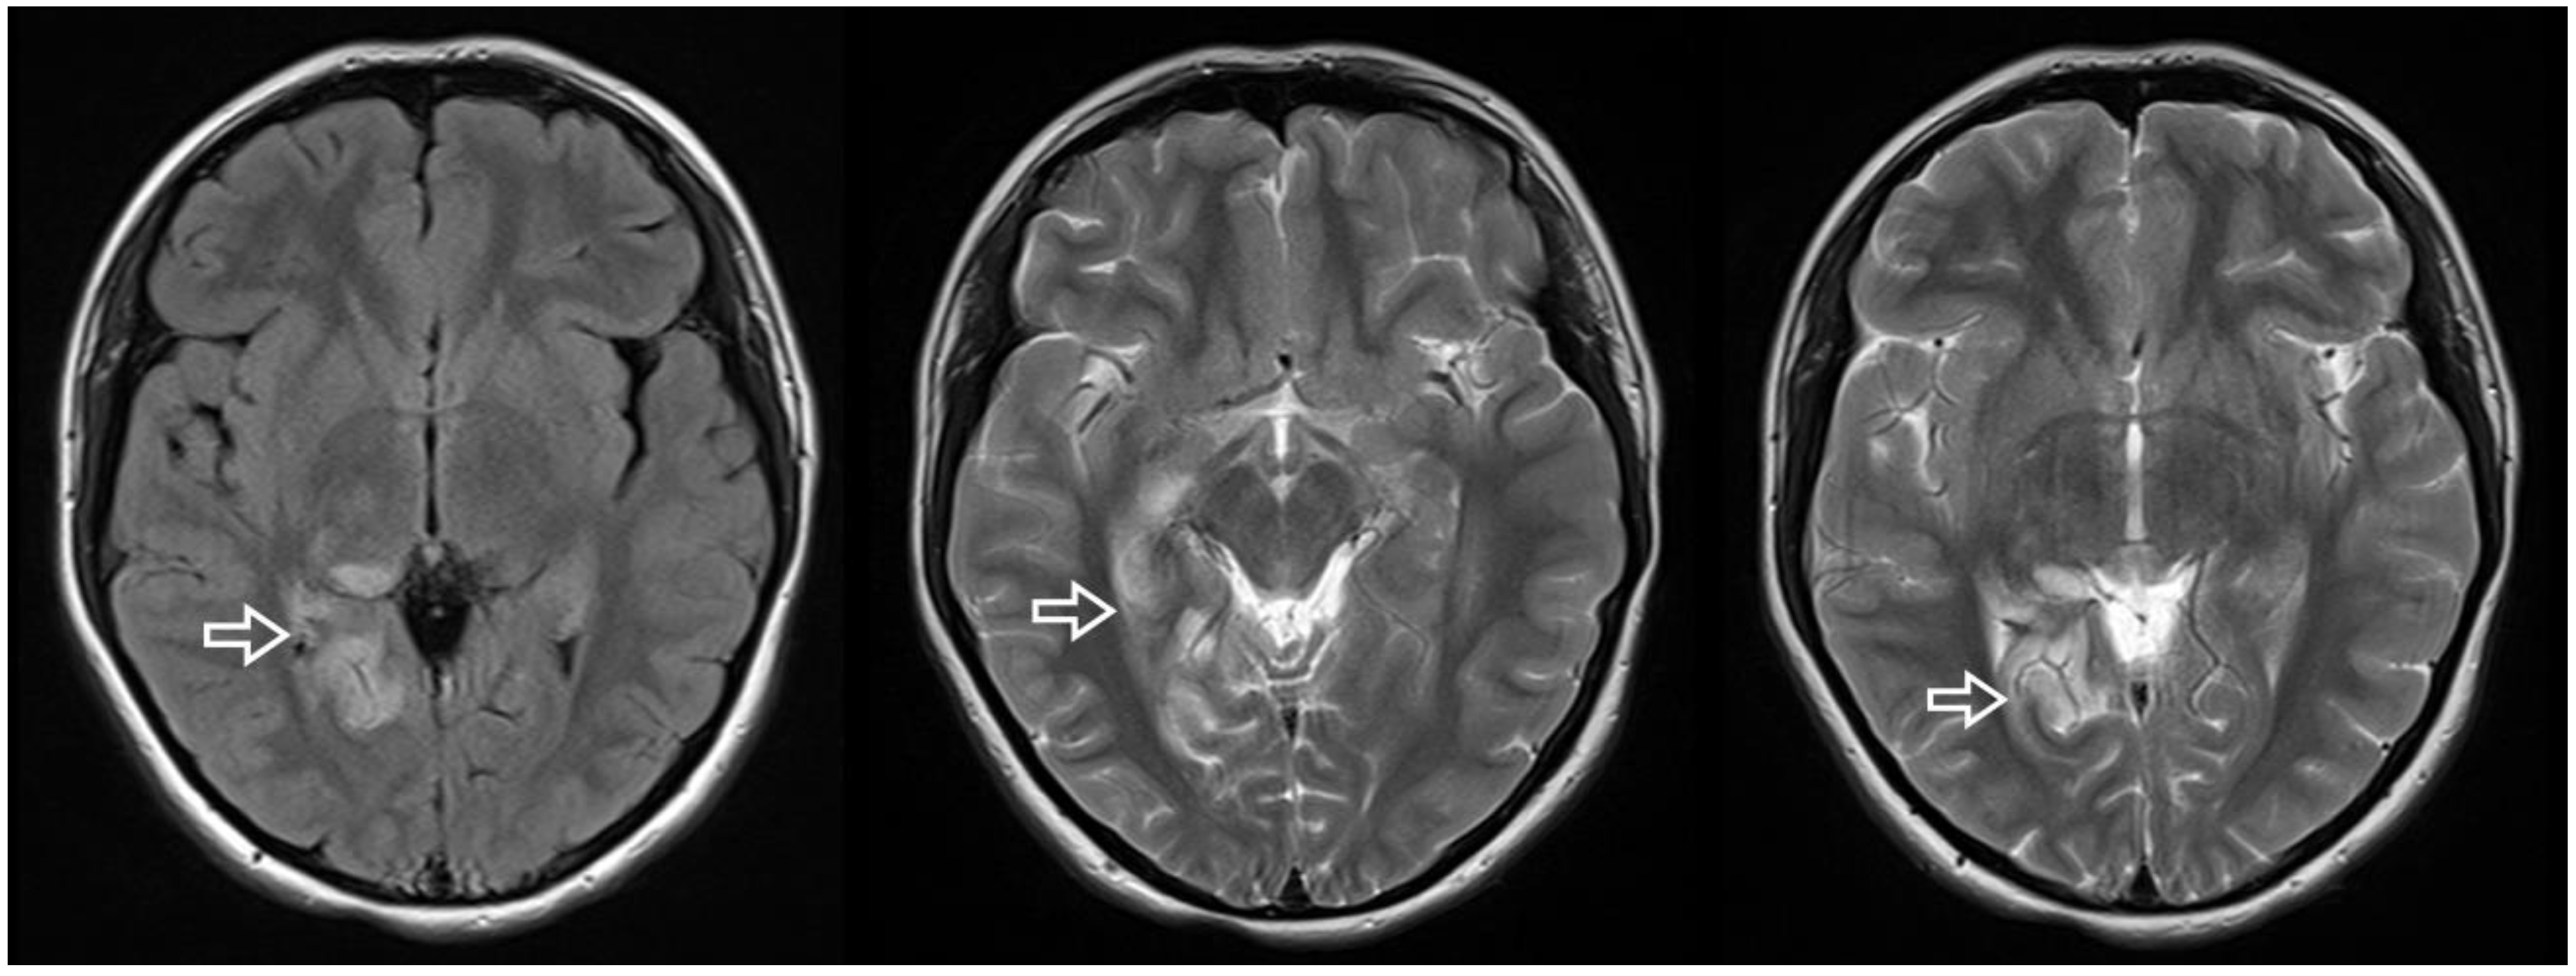

An 18-year-old woman was referred to the cardiology department in search of potential cardiac sources of embolism after suffering an ischemic stroke in the territory of the right posterior cerebral artery (Figure 1).

Figure 1.

Brain MRI axial sections showing the ischemic lesions in the territory of the right posterior cerebral artery (arrow).